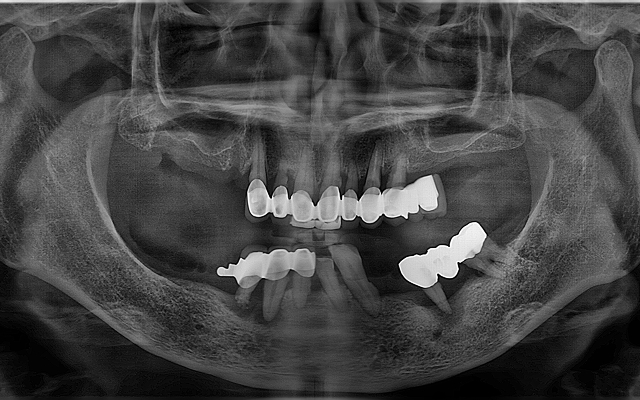

상악동 거상술 케이스

- 얇은 위턱 어금니 부위에 상악동을 거상하여 골량 보강

- 임상 경험을 바탕으로 합병증을 낮추고 예측 가능한 결과 도출